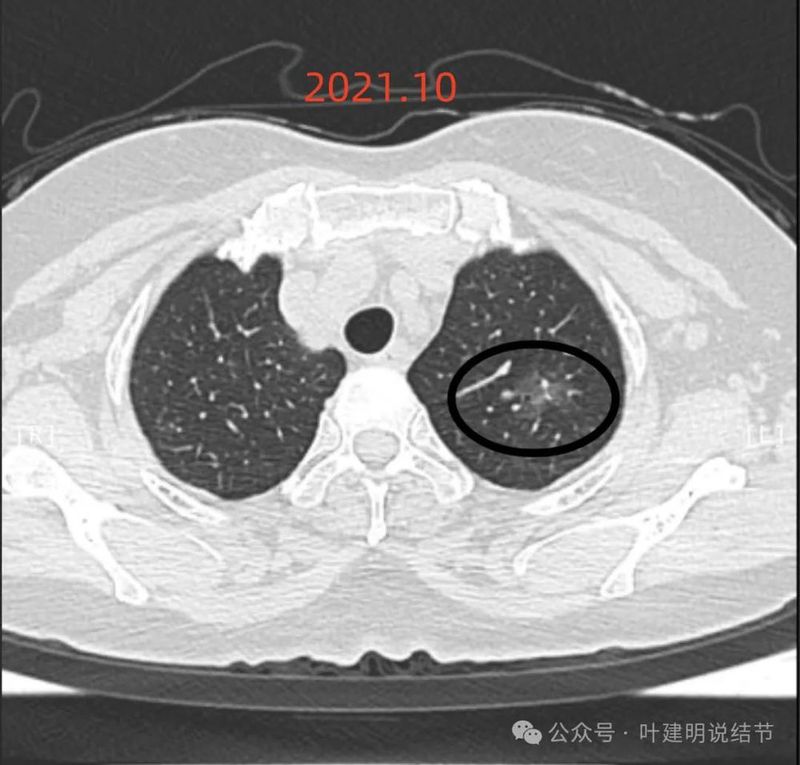

先看2021年10月时的影像:

左上叶混合密度结节,整体轮廓较清,瘤肺边界略糊,灶内有血管走行,也有细支气管扩张,表面不平,随访若持续存在,是要考虑肿瘤范畴的,微浸润性腺癌或原位癌可能性较大。